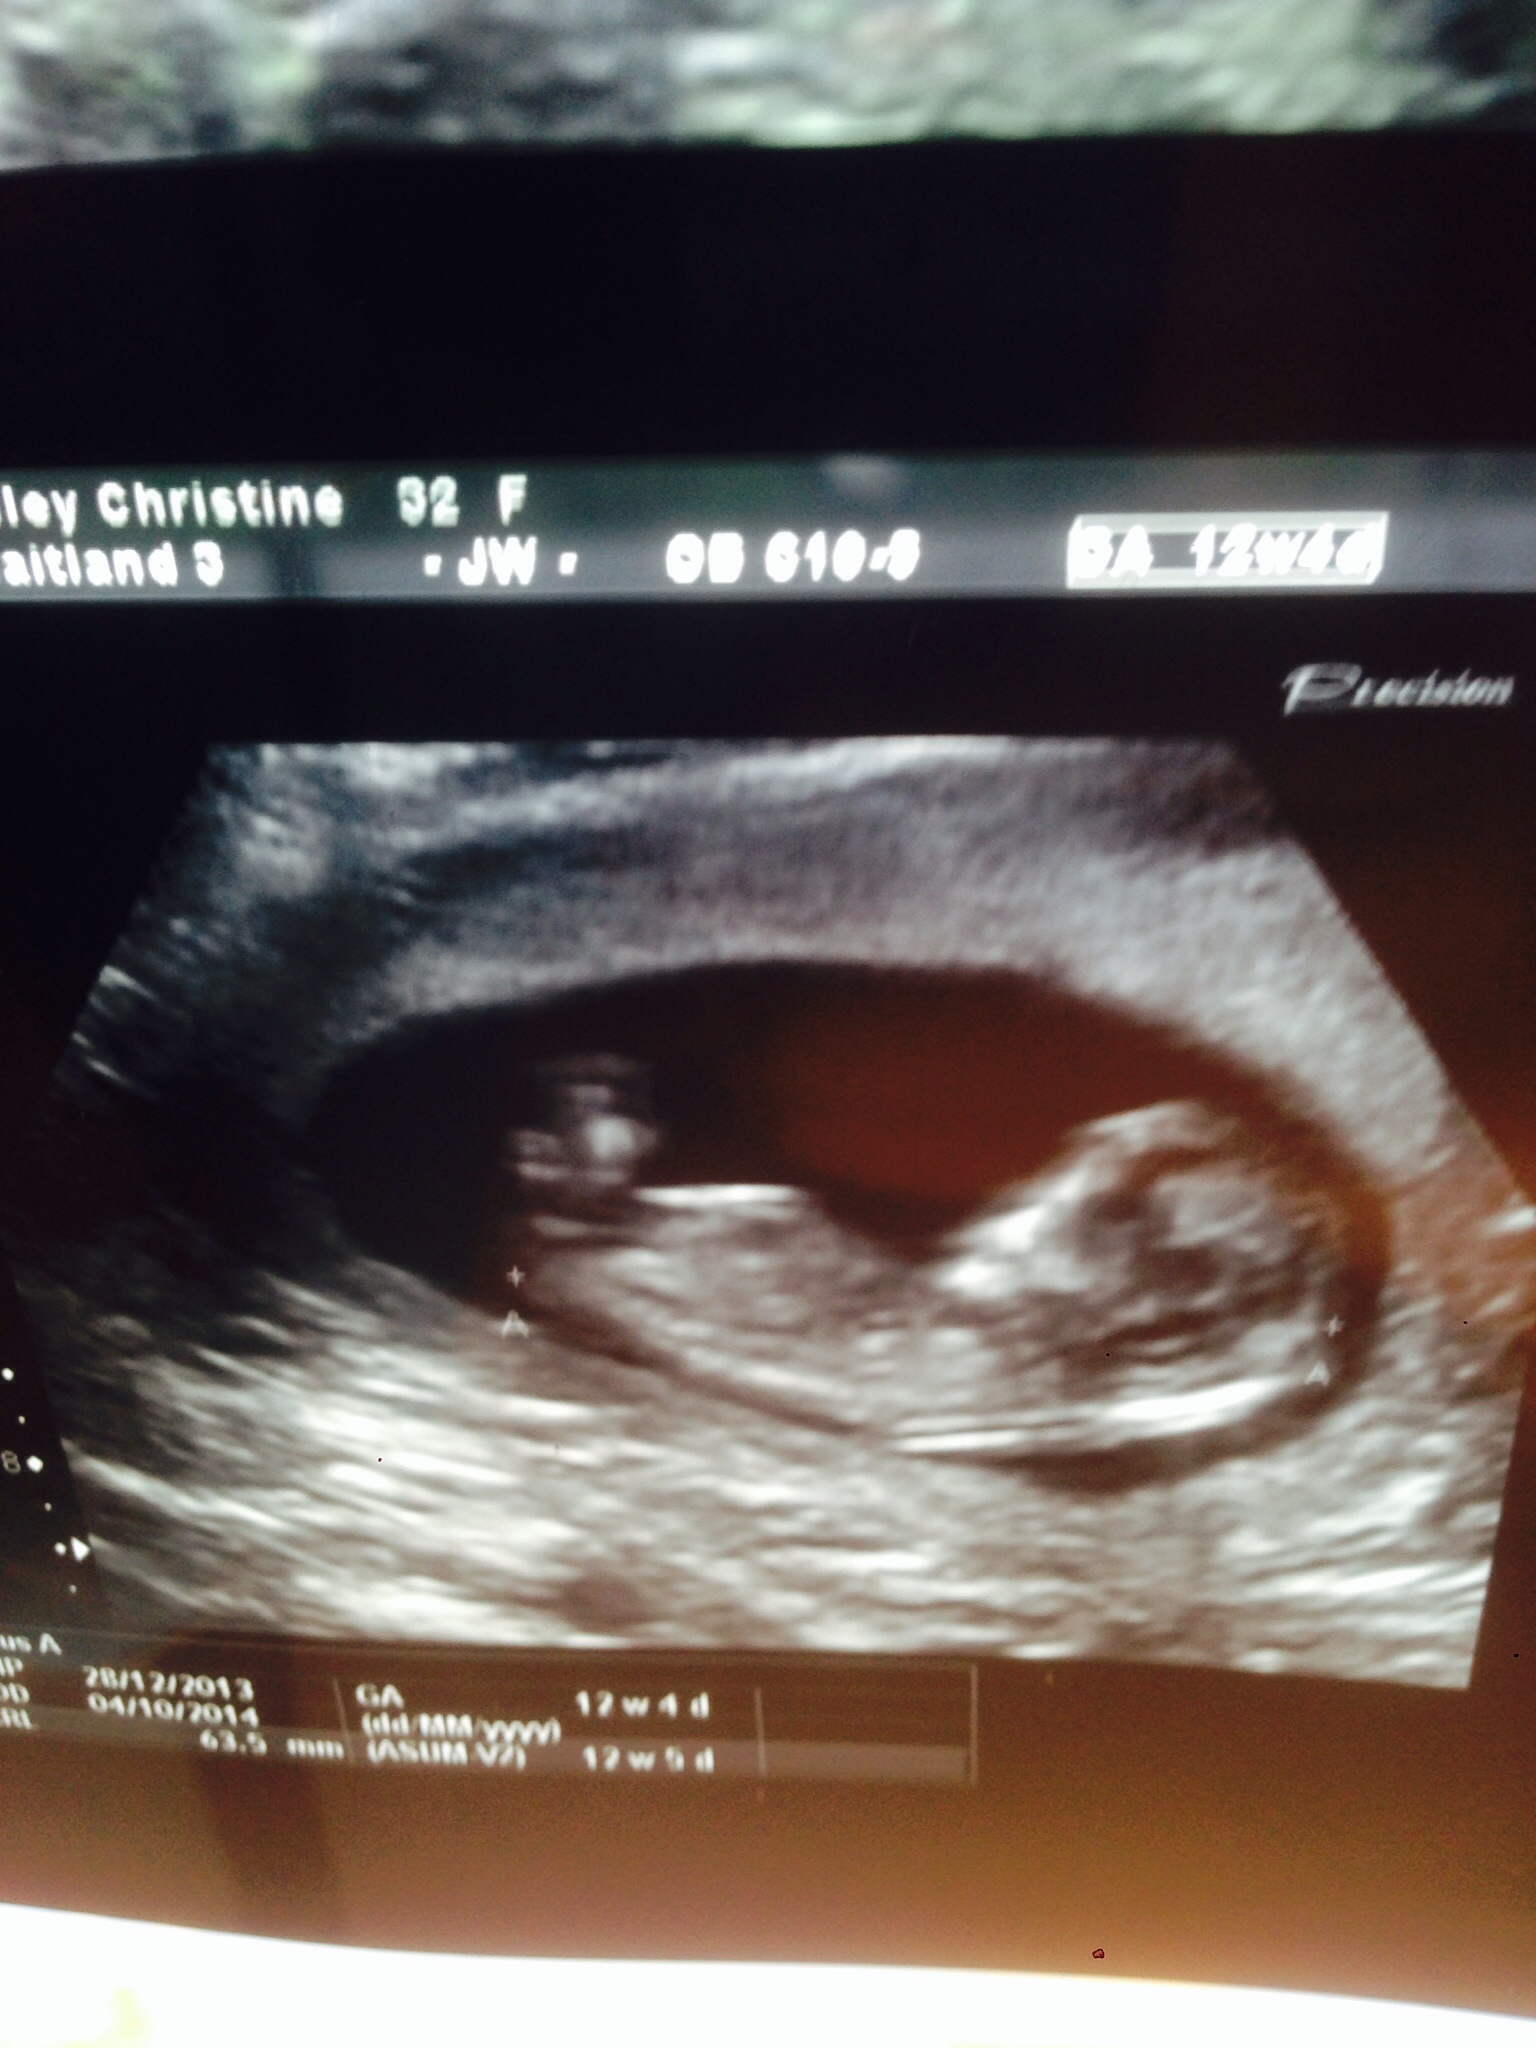

Hi this is my 12+ 4 pic any guesses for gender? Even slight leans :)Attachment 18380Attachment 18380

It looks kinda squished (the pic) but if I had to hazard a guess from what I can kinda see, I'd guess girl...but really not sure that's the nub so...

I am thinking that is a girl... the picture looks a little off but I think what I am seeing is a good girl nub!

Thinking girl

I'm saying girl :)

Leaning girl, please update when you know